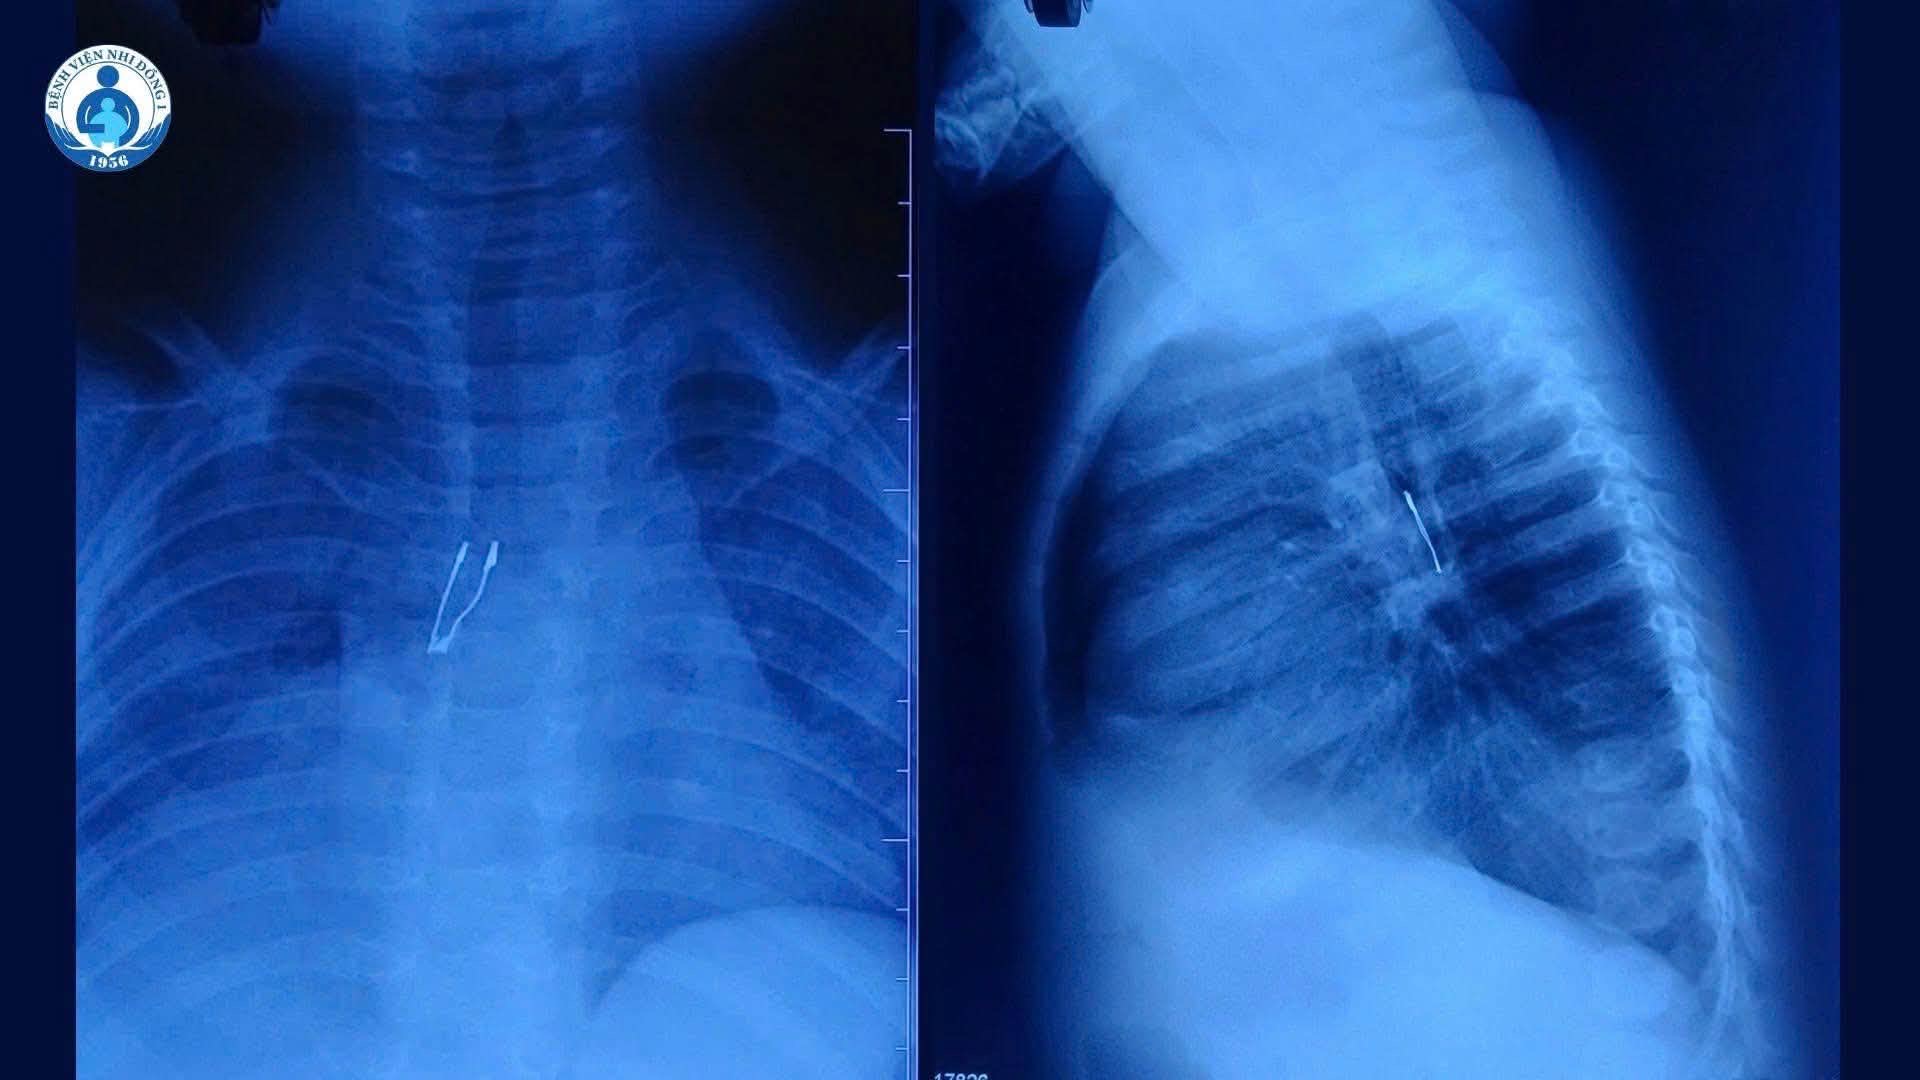

Hình ảnh X-quang cho thấy dị vật nằm ở phế quản gốc phải bệnh nhi

Tại bệnh viện, kết quả chẩn đoán cho thấy dị vật cản quang nằm ở phế quản gốc phải, kèm theo tình trạng xẹp phổi phải không hoàn toàn và tràn khí trung thất.